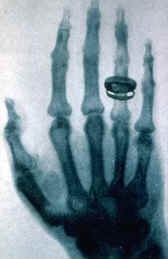

1895年10月,德国实验物理学家伦琴(Wilhelm Konrad Rontgen,1854~1923)(左图)也发现了干板底片“跑光”现象,他决心查个水落石出。伦琴吃住在实验室,一连做了7个星期的秘密实验。11月8日,伦琴用克鲁克斯阴极射线管做实验, 他用黑纸把管严密地包起来,只留下一条窄缝。他发现电流通过时,两米开外一个涂了亚铂氰化钡的小屏发出明亮的荧光。如果用厚书、2-3厘米厚的木板或几厘米厚的硬橡胶插在放电管和荧光屏之间,仍能看到荧光。他又用盛有水、二硫化碳或其他液体进行实验,实验结果表明它们也是“透明的”,铜、银、金、铂、铝等金属也能让这种射线透过,只要它们不太厚。使伦琴更为惊讶的是,当他把手放在纸屏前时,纸屏上留下了手骨的阴影。伦琴意识到这可能是某种特殊的从来没有观察到的射线,它具有特别强的穿透力。伦琴用这种射线拍摄了他夫人的手的照片,显示出手的骨骼结构。(右图)